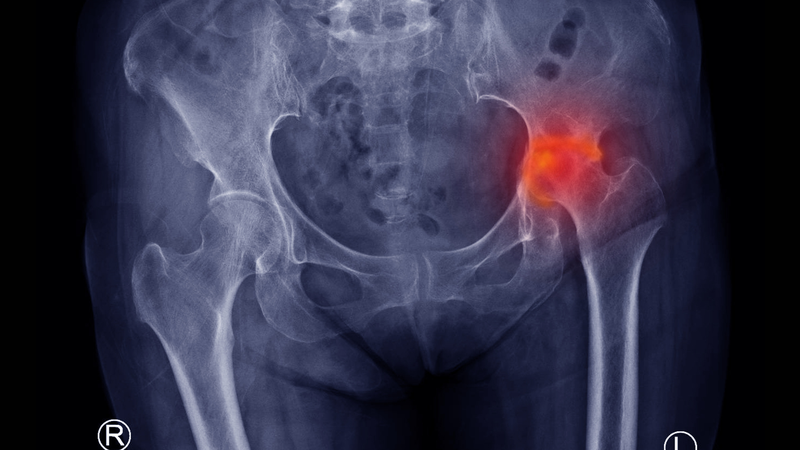

Hoại tử khớp háng: Nguyên nhân, triệu chứng và phương pháp chẩn đoán

Hoại tử khớp háng, hay còn gọi là hoại tử vô khuẩn (hoại tử xương do thiếu máu cục bộ), là tình trạng thoái hóa xương do hoại tử các tế bào xương, thường xảy ra khi cung cấp máu dưới sụn bị gián đoạn. Căn bệnh này còn được gọi là hoại tử vô mạch (hoại tử do thiếu máu), chủ yếu ảnh hưởng đến các khớp chịu trọng lực như khớp háng, khớp gối và chỏm xương đùi hoặc cánh tay, ít gặp ở các xương nhỏ hoặc xương dẹt. Nam giới có tỷ lệ mắc bệnh cao hơn.

• X-quang: Phim chụp X-quang khớp háng thẳng, nghiêng và kiểu đùi chếch là công cụ đầu tiên dùng để phát hiện hoại tử khớp háng. Ở giai đoạn nhẹ, có thể thấy hình ảnh xương thưa, với mức độ xẹp chỏm từ nhẹ đến nặng, nghiêm trọng nhất là mất một phần hoặc toàn bộ chỏm, kèm theo hình ảnh hẹp khe khớp.